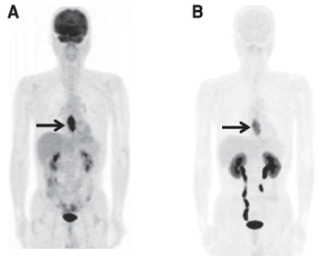

211At-AAMT:

アミノ酸トランスポーターLAT1を

介したターゲティング

がん細胞特異的に発現するLAT1の基質を開発、PETイメージングを実施済